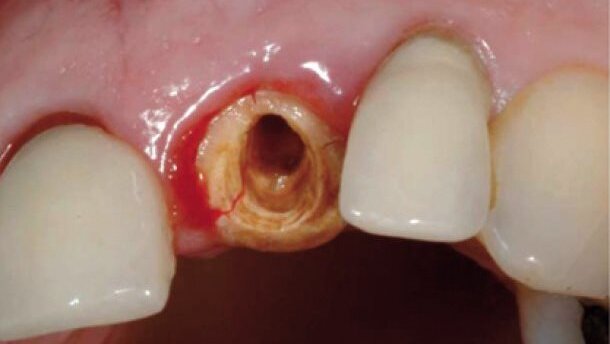

W przednim odcinku szczęki objętość kości i grubość blaszki korowej mają decydujące znaczenie dla rezultatów estetycznych odbudowy implantologicznej. Z tego względu wszczepienie implantu po ekstrakcji wiąże się dla lekarza z wieloma trudnościami.12 Do wybrania odpowiedniego sposobu wszczepienia implantu konieczna jest dokładna diagnoza przed zabiegiem, której celem jest ustalenie parametrów dziąsłowych i kostnych dla ustalenia najlepszego momentu ekstrakcji zęba i wszczepienia implantu, a także dla podjęcia decyzji, czy obciążenie implantu powinno być natychmiastowe, czy opóźnione (Ryc. 1-5).13

Implantacja natychmiastowa po każdej ekstrakcji sprzyja zachowaniu kości i dziąsła, skraca czas leczenia pacjenta, a przez to ma bardziej zachowawczy charakter (Ryc. 6 i 7).14,15 Kiedy ząb ze złymi rokowaniami pozostaje w łuku, dobór terminu ekstrakcji, natychmiastowa implantacja i zaopatrzenie wszczepu mogą nie zachować ściany zębodołu, a w szczególności zewnętrznej ściany korowej, która jest najbardziej wrażliwa w przednim odcinku szczęki przy cienkim przyzębiu i bardziej narażona na recesję dziąseł. Implantacja natychmiastowa z koroną tymczasową może jednak zachować objętość i profil zarysu tkanki miękkiej przy grubym przyzębiu.16